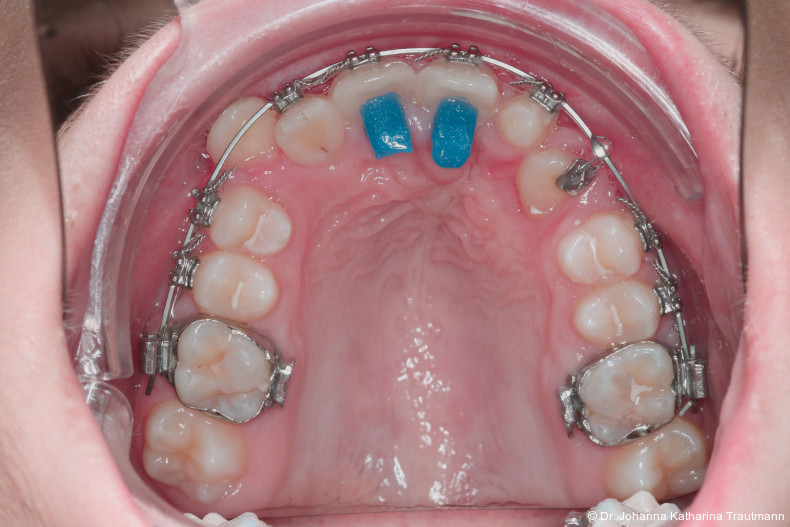

Nach transversaler Nachentwicklung der Maxilla mittels GNE nach Veltri wurde der Zahn 23 geschlossen freigelegt und an einem individualisier ten TPA nach distal angebunden. Zur Aufrichtung der Front und Mesialisierung des hypoplastischen Zahnes 22 kam zusätzlich eine 2x3Mechanik zum Einsatz. Eine rein translatorische Bewegung eines Zahnes ist auch mit einer festsitzenden Apparatur schwer zu erreichen, da der Kraftansatzpunkt nicht identisch mit dem Widerstandszentrum des Zahnes ist.7 Diese Problematik kann einerseits durch das Einbringen eines Versetzungsmomentes adressiert werden, andererseits durch eine Verlagerung des Kraftansatzpunktes. Angelehnt an den von Hong et al. beschriebenen Power Arm 8 wurde hierfür palatinal an Zahn 22 ein cranial gerichteter Hook angebracht (Abb. 3). Da Zahn 22 aufgrund seiner Hypoplasie eine verkürzte Wurzel aufwies, konnte so die Distanz zwischen Widerstandszentrum und Kraftangriffspunkt effizient reduziert werden. Eine weitere biomechanische Schwierigkeit stellte das geringe Alveolarknochenangebot im Spalt bereich mesial von 22 dar. In Bereichen mit Knochendefizit verschiebt sich das Widerstandszentrum nach apikal und wie in diesem Fall zusätzlich nach distal.9, 10 Um dem erhöhten Risiko für Kipp bewegungen entgegenzuwirken, muss hier besonders auf die Steuerung des M/F-Quotienten geachtet werden. Der vestibulär durchgebrochene Zahn 13 benötigte keine Freilegung. Um seine korrekte Einstellung zu ermöglichen, wurde die Mesialwanderung des Zahnes 16 mithilfe des TPAs korrigiert sowie eine Mittellinienkorrektur nach links mittels 2x3 Mechanik durchgeführt.